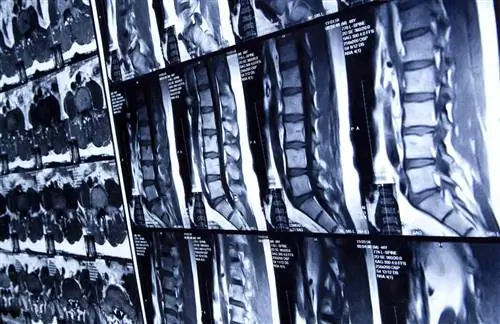

Сканирование позвоночника человека